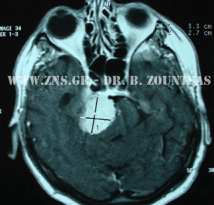

Ολική εξαίρεση μηνιγγιώματος πτέρυγας σφηνοειδούς

Ολική εξαίρεση μηνιγγιώματος λιθοειδούς αποκλίμματος